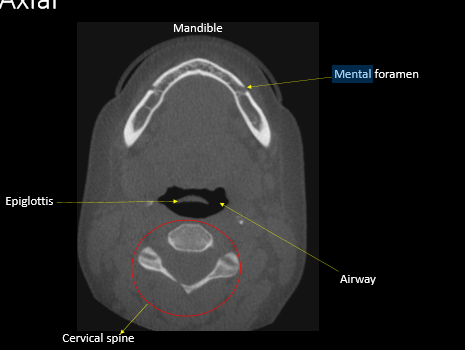

epiglottis

mental foramen

airway